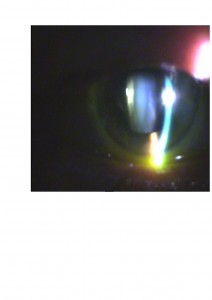

Os presentamos el caso de un paciente atendido en nuestra clínica. Presentaba una aguudeza visual OD 0,3 y OI 0,1 , con cataratas en ambos ojos (mostrada en la foto anterior). En el fondo de ojo presentaba buena coloración de las papilas y en la OCT un edema macular cistoide como os mostramos.